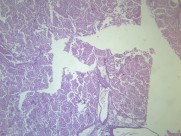

大叶性肺炎(lobarpneumonia)主要是由肺炎链球菌引起,病变累及一个肺段以上肺组织,以肺泡内弥漫性纤维素渗出为主的急性炎症。病变起始于局部肺泡,并迅速蔓延至一个肺段或整个大叶。临床上起病急骤,常以高热、恶寒开始,继而出现胸痛、咳嗽、咳铁锈色痰,呼吸困难,并有肺实变体征及外周血白细胞计数增高等。病程大约一周,体温骤降,症状消失。该病多发生于青壮年男性。疾病常见诱因有受凉、劳累或淋雨等。属于中医“风温”、“肺痈”等范畴。